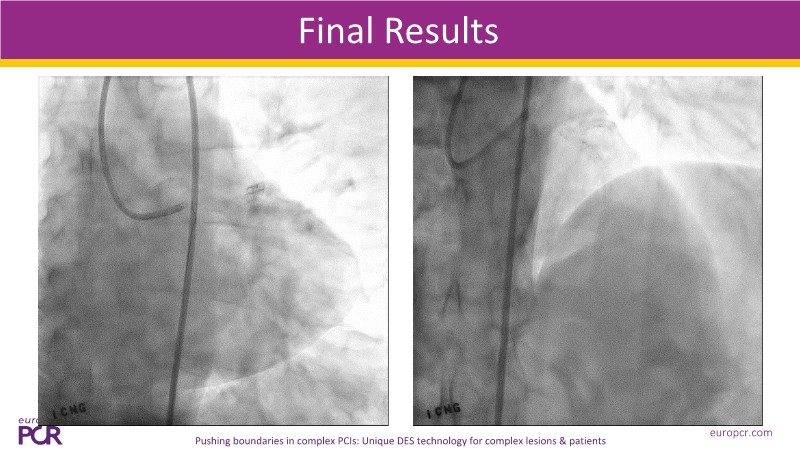

Explore cutting-edge strategies in complex PCI through four detailed clinical cases: a challenging left main bifurcation, a complex procedure using Guideliner Extension Catheters (GEC), an acute coronary syndrome intervention, and treatment of a patient with high bleeding and ischemic risks. This session demonstrates how thorough patient profiling, advanced imaging and functional assessments, and the innovative Cre8 EVO stent technology combine to optimize procedural success and long-term outcomes in complex patients.